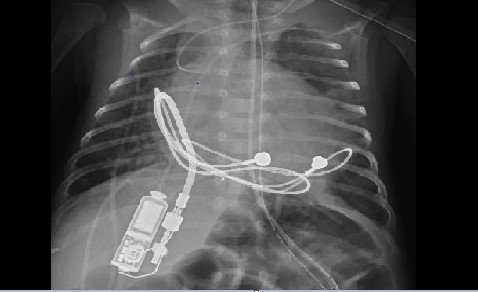

In first in-human use, UofL & Norton physicians implant tiny pacemaker, saving infant’s life